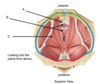

Name parts of the levator ani A, B and C

A = puborectalis

B = pubococcygeus

C = iliococcygeus